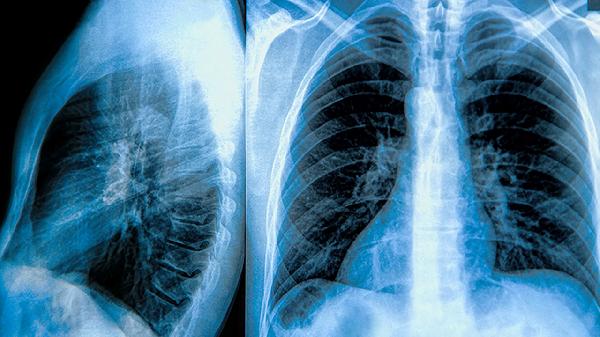

肺气囊是肺泡异常扩张形成的薄壁囊腔,常见于右肺下叶。多数患者无明显症状,常在体检时偶然发现。这类肺气囊通常由局部肺泡壁结构薄弱或慢性炎症刺激导致,直径多在1-3厘米,生长缓慢且很少影响肺功能。对于无呼吸道症状、无持续增大的肺气囊,医生多建议定期随访观察,每6-12个月复查胸部CT即可。日常需避免剧烈运动和外伤,防止囊腔破裂。

当肺气囊合并感染时可能出现咳嗽加重、黄脓痰或发热等症状,此时需考虑使用头孢克肟分散片、左氧氟沙星片等抗生素治疗。直径超过5厘米的巨型肺气囊可能压迫周围组织导致胸闷气促,或反复发生气胸,此时需胸外科评估是否行胸腔镜下肺大疱切除术。先天性肺发育异常或长期吸烟者更易出现病理性进展,这类患者应每3个月复查并严格戒烟。